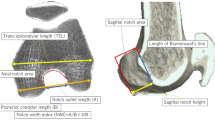

Computed tomography (CT) scans were performed on all knees after ACL reconstruction. The knee was placed in full extension. Digital Imaging and Communications in Medicine data were extracted from the picture archiving and communication system. Data were segmented by Mimics software (Materialise, Leuven, Belgium), a commercially available image processing software used to create three-dimensional (3D) surface models from stacks of two-dimensional image data. The data were then imported into Geomagic Studio software, version 12.0 (Geomagic, Rock Hill, SC, USA), and the 3D surface model was projected into coronal, axial, and sagittal planes to measure the tunnel axis angle in each plane (Fig. 3). As described by Basdekis et al. [20], the angle between the tunnel and the line tangent to the distal and posterior aspects of the femoral condyles was measured in the coronal and axial planes. The sagittal plane angle between the tunnel and the extended intersectional line of the femoral shaft was measured. A lower tunnel angle in the sagittal plane indicated that the tunnel orientation is extended compared with the femoral shaft, while a higher tunnel angle in the sagittal plane indicated that tunnel orientation is flexed compared with the femoral shaft.

Angle in each plane projected from a three-dimensional surface model. a The angle between the tunnel and a line tangent to distal aspects in the coronal plane was measured. b The angle between the tunnel and a line tangent to the posterior aspects of the femoral condyles was measured in the axial plane. c The angle between the tunnel and the extended intersectional line of the femoral shaft in the sagittal plane was measured